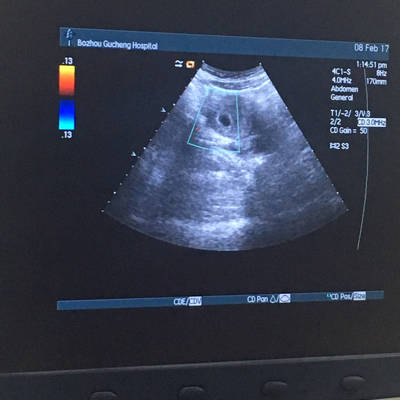

怀孕40天有很小的红色血块流出,查b超显示有孕囊,是先兆流产吗?

有妇产科医生帮忙看看这是完整孕囊吗?

图片是怀孕40天流血排出的是不是孕囊

医生您好,我六周怀孕,但是彩超没看到孕囊,晚上上厕所排出东西,昨天的

出血,现在上厕所排出这样东西,是血块还是孕囊.

早期出现阴道出血,量多,排出白色圆形或者椭圆形孕囊组织是流产的标志